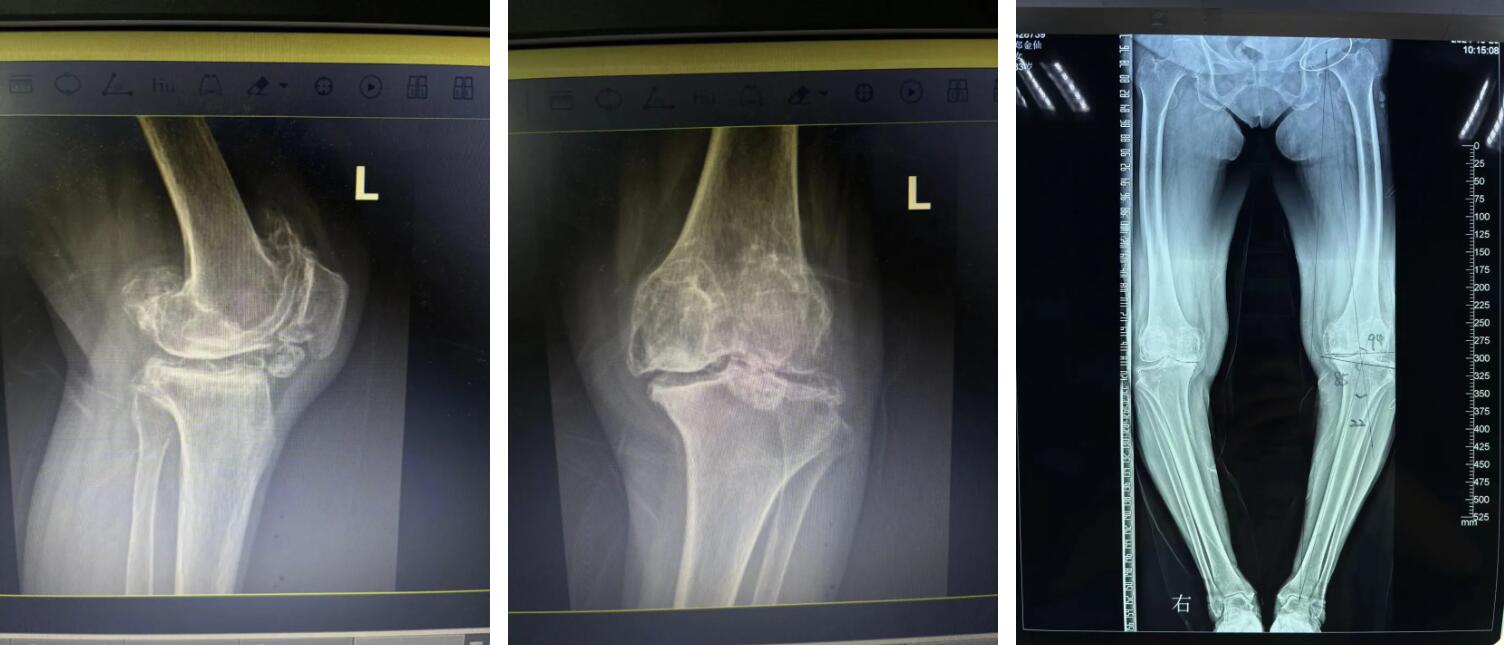

羅院長(zhǎng)仔細(xì)了解鄭阿婆的病情后,第一時(shí)間為阿婆確定了左側(cè)人工全膝關(guān)節(jié)置換手術(shù)的治療方向,并制定了詳細(xì)的治療方案,最終得到了阿婆和家屬的一致認(rèn)同。

住院后,羅院長(zhǎng)立即給阿婆安排一對(duì)一術(shù)前規(guī)劃、術(shù)前3D打印,做到了關(guān)節(jié)置換的“量身定制”,最終在羅軍手術(shù)團(tuán)隊(duì)的努力下阿婆順利完成了機(jī)器人輔助下左側(cè)人工全膝關(guān)節(jié)置換手術(shù)治療。